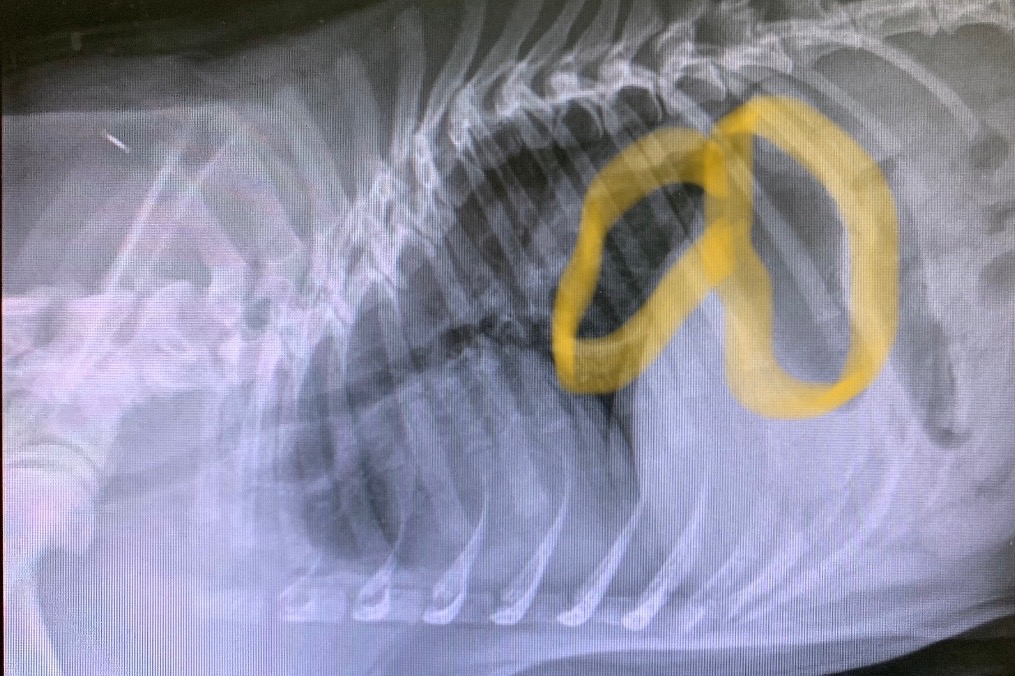

Our 7-month-old frenchie, Marvin, was just diagnosed with a Hiatal Hernia. This essentially means that his stomach is going through his diaphragm into his esophagus. His brachycephalic (flat-faced) breed breathing issues are worsening his condition. In order to correct these issues, Marvin needs surgery. We are currently giving him medications and injections to try and prevent him from regurgitating his meals, but he isn't having much luck keeping food and water down. We are feeding him small portions of wet food throughout the day by holding up his dish to keep his head elevated while he eats and continuing to elevate his head after meals to try and prevent regurgitation. Marvin is a gentle and friendly frenchie who has two cat siblings that he adores! His favourite snacks are blueberries and carrots! He is a couch potato as he loves cuddling and taking naps, but before COVID-19 he also enjoyed playing at the park with his friends. Marvin joined our family on January 4th and we can't imagine life without him. We adore everything about him, even his frenchie farts! We would do anything for him, which is why we're reaching out to whoever is able to help. COVID-19 has put a financial strain on us, his hoomans, as we are currently living off of one income and regret that we can't afford the full cost of his surgery. His surgery fees may cost up to $5000. We understand that this is a difficult time for EVERYONE mentally, physically, financially, but we are hopeful that any little bit will help. We would be forever grateful!